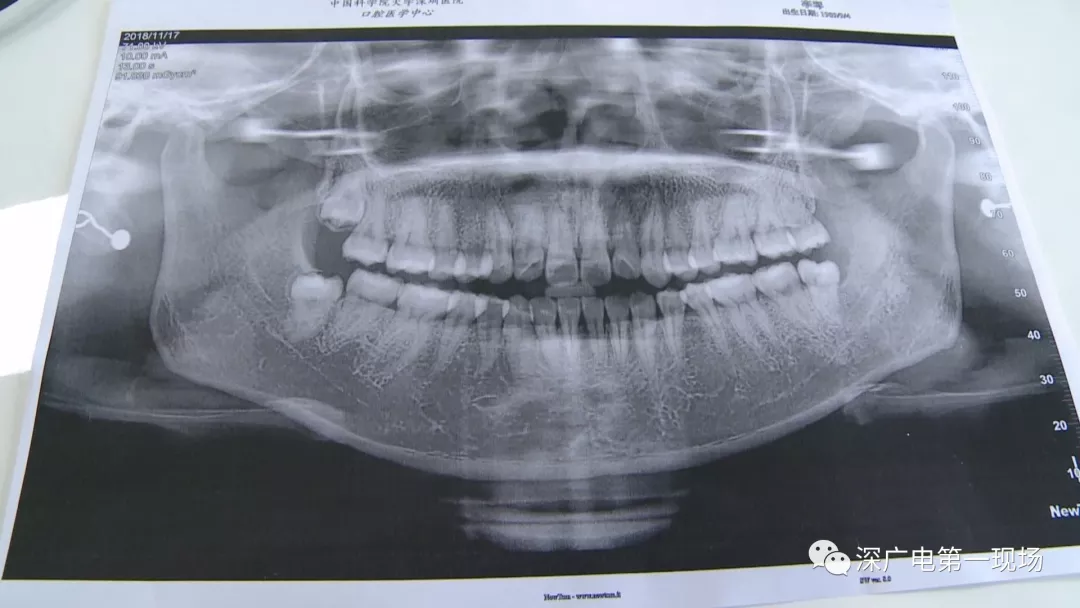

針對李女士的情況,醫(yī)生介紹,當(dāng)時(shí)要想拔出李女士的這顆智齒,難度還是很大的,屬于復(fù)雜智齒的拔除術(shù)。她的風(fēng)險(xiǎn)在于距離神經(jīng)管近,同時(shí)這顆牙齒完全埋在牙床最后的位置,直接往外拔,會(huì)加大頜骨的風(fēng)險(xiǎn),因此需要先切開,讓牙齒暴露后,切小再慢慢地拔出。